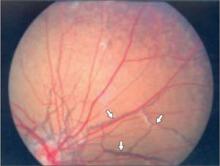

There were angioid streaks on funduscopic examination (FIGURE 2). Her lungs were clear to auscultation and percussion. Her cardiovascular exam was normal; there were no carotid bruits, and peripheral pulses were normal. The abdomen was soft and nontender; no hepatosplenomegaly or masses were present. We found no peripheral edema or cyanosis. A neurological exam was unremarkable.

FIGURE 2

Cause of the patient’s declining vision

A funduscopic exam revealed angioid streaks (arrows).

The average age of patients diagnosed with pseudoxanthoma elasticum skin abnormalities is 22 years.3 Risk of cardiovascular disease may correlate with the presence of angioid streaks of the fundus—irregular, reddish-brown, or gray lines radiating from the optic disc.4 Patients may have severe ophthalmologic or cardiac disease with little or no skin involvement, or vice versa.5-8 Onset, progression, and severity of the disease vary considerably among patients.8,9